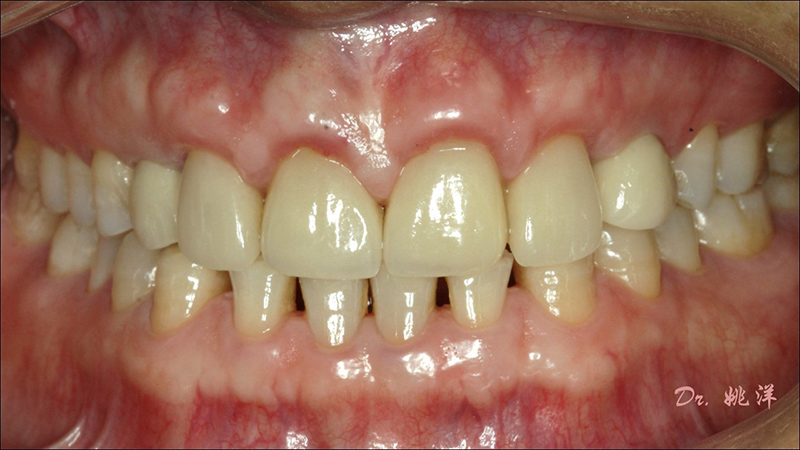

種植后數(shù)字化取模,前牙美學(xué)間隙精確分配

從最終修復(fù)效果可以看出:23,24間隙不足修復(fù)兩顆,修復(fù)為1顆牙。因?yàn)榻?jīng)過(guò)數(shù)字化設(shè)計(jì)和精確導(dǎo)航植入,修復(fù)體齦緣協(xié)調(diào)自然

術(shù)后照片

恢復(fù)了正常的淺覆合淺覆蓋